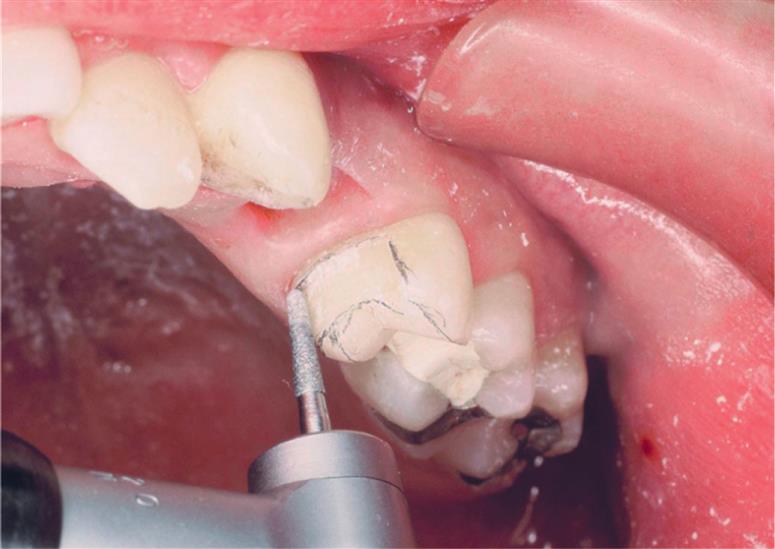

The step-by-step preparation of a three-quarter crown is illustrated on a maxillary premolar (Fig. 11.4). Except for a narrow bevel or chamfer margin placed along the bucco-occlusal line angle, the buccal surface of the abutment remains intact. The other surfaces (including the occlusal surface) are prepared to accommodate a casting in the same manner as a complete crown preparation (see Chapter 8), differing only in the need for proximal axial grooves to develop resistance form.

Upon the completion of occlusal reduction, the clearance on the functional cusp should be at least 1.5 mm, and those on the nonfunctional cusp and in the central groove should be at least 1.0 mm. Simultaneously, the tooth should be prepared so that metal display is minimal; the original outline form of the buccal wall should be preserved as well as possible.

The proximal grooves are best prepared with a tapered tungsten carbide bur.

Depending on available access, it may be feasible to complete the flaring with the same rotary instrument that was used to place the groove (Fig. 11.13). However, removing the last “lip” of unsupported tooth structure with a chisel is often a better option because this minimizes the risk of damage to the adjacent tooth.